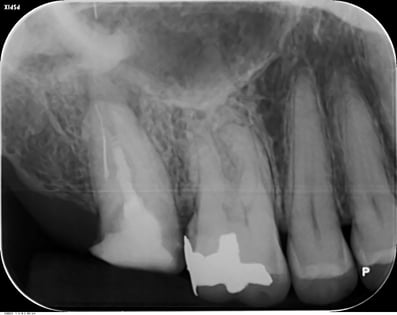

1年後

根尖の透過像も消失し、自覚症状(咬合痛などもありません)安心して最終印象採得(型どり)を行いました。

当院では、CTやレントゲンを撮影して悪い像(根尖などのX線透過像)が消失するのを確認してから補綴するようにしています。

透過像が残っているまま、治療を終了させるアメリカ的な合理主義的な考え方には断固として共感できませんね。